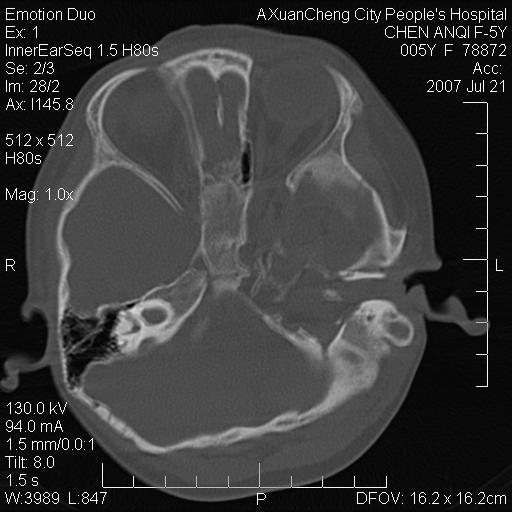

标题: PED0273:5岁,左耳流脓痛疼一周,颅底骨质破坏 [打印本页]

标题: PED0273:5岁,左耳流脓痛疼一周,颅底骨质破坏

患儿5岁,左耳流脓痛疼一周,左外耳道肉芽组织填塞 软组织窗显示病灶内结节状低密度影为气体密度

左侧中耳炎并胆脂瘤,左颞骨岩部骨质破坏并颅内感染积气。